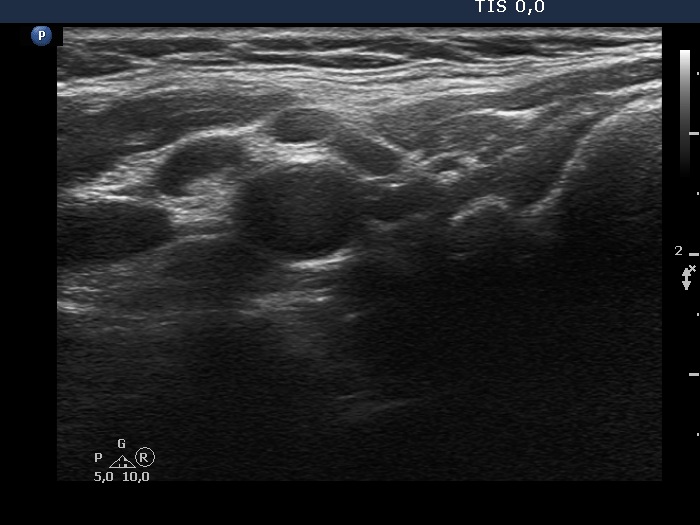

Ultrasonography. The thyroid was echonormal. There was a hypoechogenic nodule in the right lobe. The nodule had numerous punctate echogenic granules.

The echogenic figures are very difficult not to interpret as microcalcifications. Nevertheless, thorough analysis reveals that some of the bright granules has a short tale, and great proportion of these figures are related to ventral tiny hypoechoic areas, probably cysts. Moreover, there are not only echogenic granules but also short echogenic lines within the nodule. Taking all in all, these echogenic figures are very suspicious being microcalcifications.

In such nodules it is to be considered to delay the ultrasound report till the result of FNA. In this patient FNA disclosed benign colloid goiter and there were macrophages on the smear. The latter proved that the nodule had cystic areas. If we take this fact into account, then it can solve our concern about the interpretation of echogenic granules.